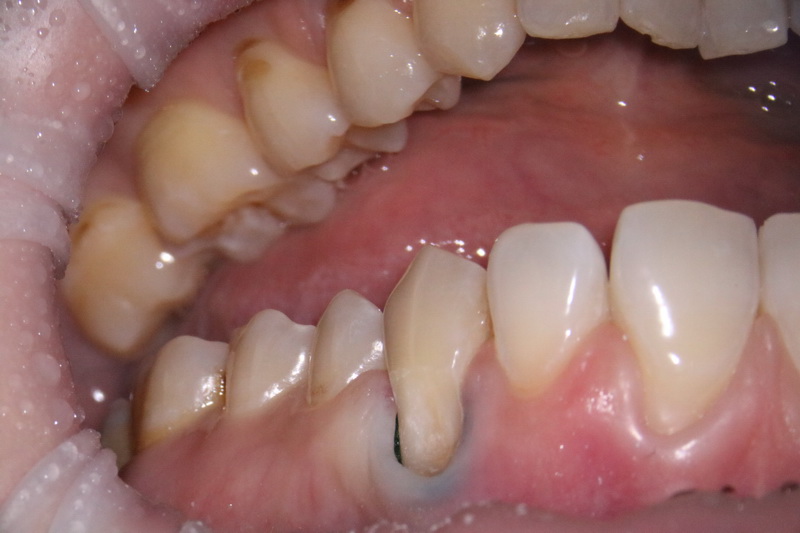

Клиноподібний дефект – це некаріозний дефект емалі, що розташовується на вестибулярній поверхні зуба в пришийковій зоні, тобто зі сторони губ та щік біля ясен.

Неправильний прикус призводить до локального перевантаження зубів і як наслідок емаль тріскається в ділянках пришийкових зон.

Клиноподібний дефект сам по собі зникнути не може і з часом це призводить до повного стирання твердих тканин в пришийковій ділянці і як наслідок виникають переломи або сколи зубів.

Часто стоматологи працюють тільки з симптомами цієї патології, бо не досконало розуміють сутність проблеми, і як наслідок цього клиноподібний дефект нікуди не зникає а тільки збільшується, що в ітозі призводить до сколу зуба.